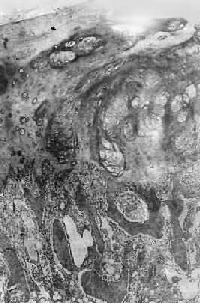

镜下,骨肉瘤由明显间变的梭形或多边形肉瘤细胞组成,细胞大小不等,核形奇异,大而深染,核仁明显,易见病理性核分裂像。肿瘤细胞直接形成肿瘤性类骨组织或骨组织,是诊断骨肉瘤的最重要的组织学依据。所形成的类骨组织或骨组织在不同肿瘤或同一肿瘤的不同部位多少不等。往往可看到肿瘤性骨质发生过程中各阶段的形态,最早期在恶性肿瘤细胞间出现均质红染的胶原样物质,其后红染物质逐渐增多,将肿瘤细胞分隔疏远,构成小梁或片状的肿瘤性类骨组织(图17-8)。类骨组织可伴钙盐沉着,其内的肿瘤细胞固缩变小,形成肿瘤性骨质。骨肉瘤内也可出现肿瘤性软骨(图17-9)。

图17-8 骨肉瘤

多形性肉瘤细胞直接形成肿瘤性骨样组织